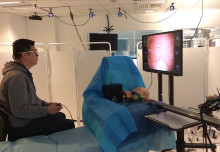

Leading infection experts came together to explore clinical challenges in infection and how Imperial’s interdisciplinary expertise can solve them.